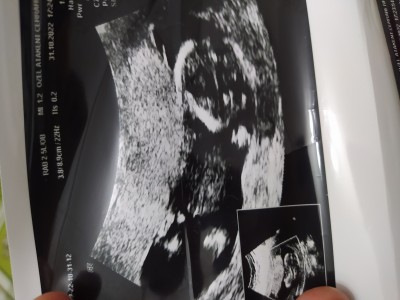

banada bakin

image

sizce benimkinin cinsiyeti ne bide siz yorumlayin:)))

Ben cinsiyetini biliyorum sadece merk ettim ne diceksiniz kel ilac muhabbetine girdigin gibi cik istersen canim benim bebegim erkek:))

Bencede bu bebek kıza benziyor Dr yanılmış olabilir mi